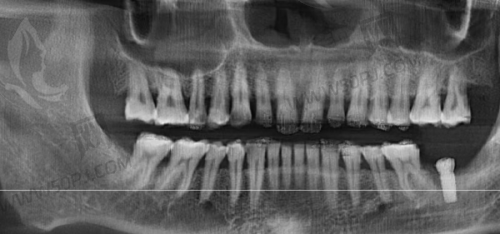

二、设备精良不打折,“拿得出手”的技术不是空谈

现在口腔诊疗讲究一个字:精!而瑞兴口腔医院引进了多种进口高端诊疗设备,比如数字化3D种植导航、口腔CT、显微镜种牙、德国西诺德牙椅等。别小看这些“电动玩具”,确实改变了过去只靠眼就是干的时代,精度高、创伤小、修复快,还能事前3D建模、精密植入,真正做到”种牙不靠瞎蒙,全靠导航定位”。要知道,在上海要配齐这些设备的私立医院,可没几家。